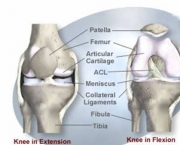

Também conhecida como gonartrose, a osteoartrose do joelho é uma enfermidade degenerativa e inflamatória que resulta na destruição da cartilagem das articulações levando à deformidades nelas. Normalmente a degeneração cartilaginosa começa com o envelhecimento do indivíduo.